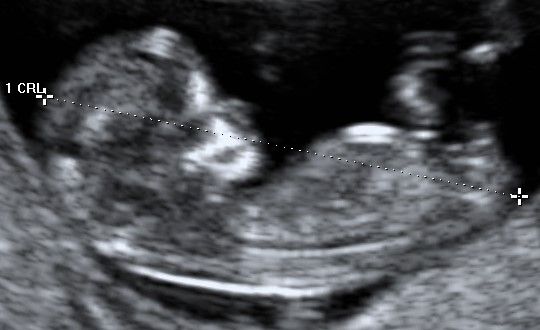

Ecografia Obstetrica y ginecologia

Ecografia Doppler obstetrica

Ecografia volumétrica (3 D y 4D)